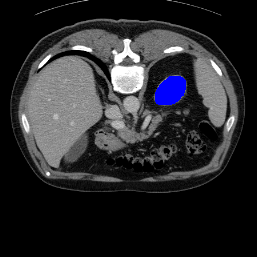

In order to assess the performance of the proposed method, we compare the performance of the proposed model with excellent models in recent years. Table 1 and Table 2 shows the comparison results of different models in setting1, while Table 3 and Table 4 shows the comparison results of different models in setting2 on the data set in recent years. PANet[25] is the most widely influential few-shot model in the field of few-shot image segmentation on natural images. SENet [18] is the first few-shot segmentation model proposed for medical images. SSL-ALPNet[19] introduced the milestone of using superpixel self-supervision to train few-shot medical image models. RPNet[29] is a supervised method with a recursive mask optimization module to iteratively optimize the segmentation mask, [27] adapt it into the same self-supervision learning framework and applies setting1 to it and denoted as SSL-RPNet; CRAPNet[27] is the latest SOTA model for 2023. Compared with CRAPNet, our method outperforms most of the state-of-the-art models and only slightly outperforms CRAPNet. Figures 3 and 4 show examples of the model’s segmentation predictions on different datasets, respectively; The first row is the support map, the second row is the label map, and the third row is the segmentation prediction of the model.